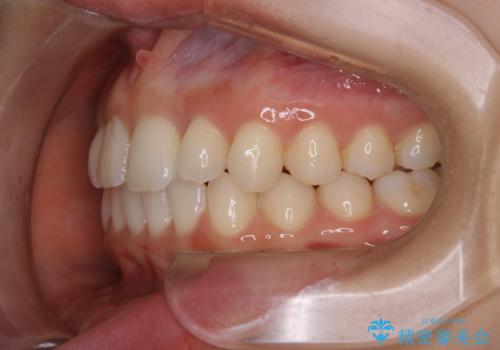

- 前から2番目の歯が捻じれていることが気になるとご相談にいらした方です。

インビザラインFULLで治療を行いました。

上の前から2番目の歯は、一般的に周囲の歯と比べて小さく、動きづらい歯であると言われています。前歯にゴムかけを行うことで理想的な位置まで歯を動かしてくることが出来ました。